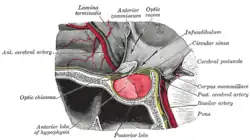

| The pituitary gland on a plate from Gray's Anatomy (1918). The anterior lobe is on the left, and the posterior lobe on the right, both in red. | |

The pituitary gland is located at the base of the brain, and intimately connected with the hypothalamus. It consists of two lobes: the posterior pituitary, which consists of nervous tissue branching out of the hypothalamus, and the anterior pituitary, which consists of hormone-producing epithelium. The posterior pituitary secretes antidiuretic hormone, which regulates osmolarity of the blood, and oxytocin, which causes contractions of the uterus in childbirth and participates in breastfeeding.[14]